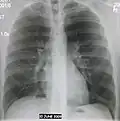

- Left upper lobe pneumonia with a small pleural effusion.